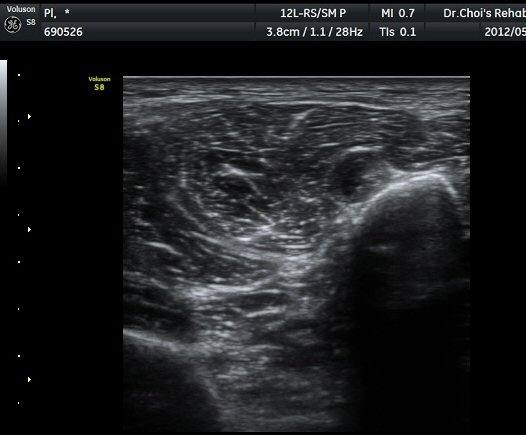

ŽÃËÀÚ¸¦ ´õ ¾Æ·¡·Î À̵¿ÇÏ´Ï Ãµºñ°ñ½Å°æÀÌ Àú¿¡ÄÚ µÕ±Ù µ¢¾î¸®·Î °üÂûµÇ´Ù°¡ ´Ù½Ã Á¤»óÀûÀÎ ¸ð½ÀÀ¸·Î °üÂûµÈ´Ù(±×¸² 7, 8).